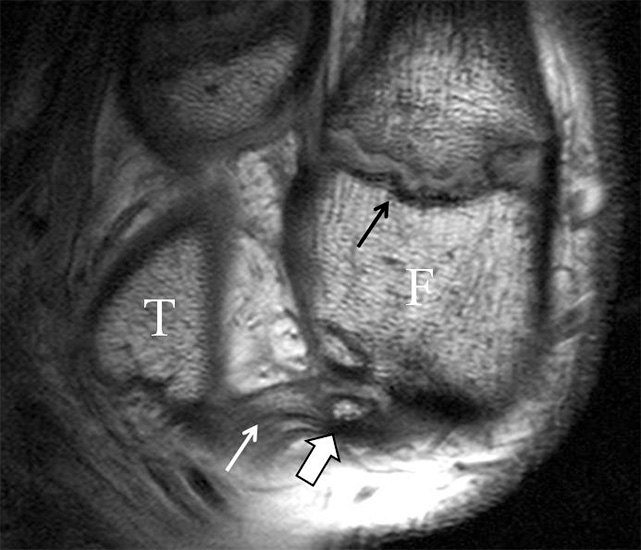

b. T2 fs axial. Infraktion des hinteren Volkmann‘schen Dreiecks (schmale, weiße Pfeile). Hier inserierende, intakte, hintere Syndesmose (breite, weiße Pfeile).

Abbildung 18b

Das Ligamentum tibiofibulare posterius (hintere Syndesmose) verläuft flacher und geht nach kranial in das Ligamentum tibiofibulare interosseus und nach kaudal in das Ligamentum intermalleolare posterius über. Letzteres bildet ein artikuläres Labrum zwischen Trochlea und Talus 9.

Da also die hintere Syndesmose an der posterioren Tibia inseriert, entspricht eine Fraktur oder Infraktion des hinteren Volkmann`schen Dreiecks funktionell einem knöchernen Ausriss des Ligamentum tibiofibulare posterius (Abb. 18 a und b). Aufgrund der Koinzidenz von Syndesmosenläsionen mit Innenbandverletzungen ist bei der Beurteilung gesondert auf solche zu achten.